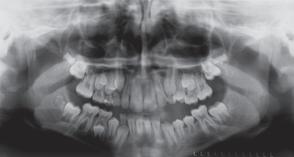

Blandt tandstillingsfejl anses transposition for det vanskeligste at korrigere. Accepteres transpositionen, vil en nivellering ofte føre til et resultat, der både funktionelt og æstetisk er utilfredsstillende. Ikke desto mindre er accept af en transposition den dominerende behandlingsstrategi, hvis man skal dømme efter kasuistikker i litteraturen.

Formålet med denne artikel var at præsentere en litteraturoversigt over forekomsten og ætiologien samt diskutere de »cost-benefit«-overvejelser, som har haft indflydelse på behandlingsstrategien og på beslutningen om at acceptere eller korrigere. Et andet formål var at diskutere behandlingen af 12

patienter med transpositioner; otte mellem hjørnetænder og 1. præmolar og fire mellem hjørnetænder og laterale fortænder. Hos de ni patienter blev transpositionen korrigeret inden for normal behandlingstid. Dette kunne tilskrives, at behandlingen blev foretaget med et segmenteret apparatur, der tillod differentiering mellem aktive og passive enheder, og som var designet således, at det optimale kraftsystem blev påført de tænder, der skulle flyttes. To patienter blev behandlet med ekstraktioner, en pga. parodontale problemer og en anden pga. trangstilling. Transpositionen blev accepteret hos en patient, fordi tandretningen var påbegyndt af anden tandlæge.

Ciarlantini R, Melsen B. Maxillary tooth transposition: Correct or accept? Am J Orthod Dentofacial Orthop 2007; 132: 385-94.